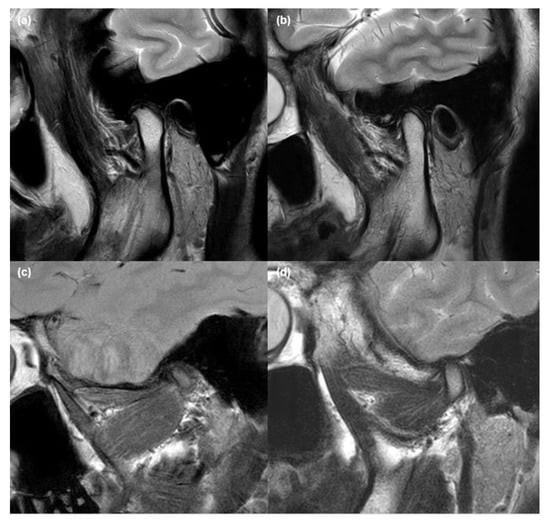

2.2. MRI Acquisition and Analysis

2.3. Validation of MRI Findings